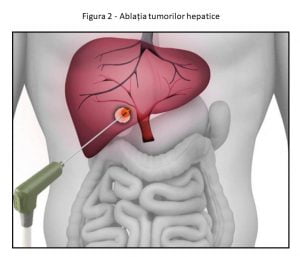

Ce este ablația în tumorile hepatice?

Ablația se referă la distrugerea tumorilor folosind ace speciale sau sonde plasate în tumoră percutan, sub îndrumarea imagistică.

Poate fi utilizat pentru tratarea tumorilor la diferite organe, cum ar fi ficatul, plămânii, oasele etc. Încălzirea (radiofrecvența sau ablația cu microunde), înghețarea (crioablarea) sau agenții chimici (ablația de alcool) sunt utilizate pentru a distruge celulele canceroase. Atât tumorile hepatice primare, cât și metastatice cu dimensiuni și numere limitate (<5 cm până la 5 leziuni) pot fi tratate prin ablație.

Poate fi utilizat pentru tratarea tumorilor la diferite organe, cum ar fi ficatul, plămânii, oasele etc. Încălzirea (radiofrecvența sau ablația cu microunde), înghețarea (crioablarea) sau agenții chimici (ablația de alcool) sunt utilizate pentru a distruge celulele canceroase. Atât tumorile hepatice primare, cât și metastatice cu dimensiuni și numere limitate (<5 cm până la 5 leziuni) pot fi tratate prin ablație.